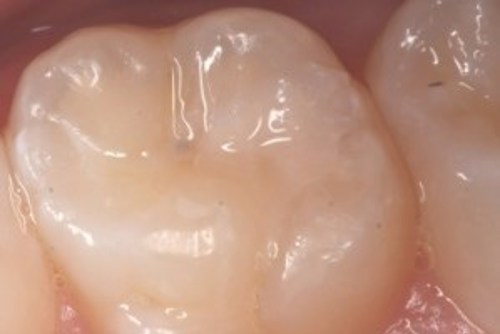

Hullet bliver lavet

Billederne nedenfor viser, hvordan hullet bliver lavet.

På første billede ses hullet som en sort plet på tanden.

På andet billede er tandoverfladen boret væk, så man kan se ned i hullet.

På sidste billede er hullet renset og der er lagt en plastfyldning i.